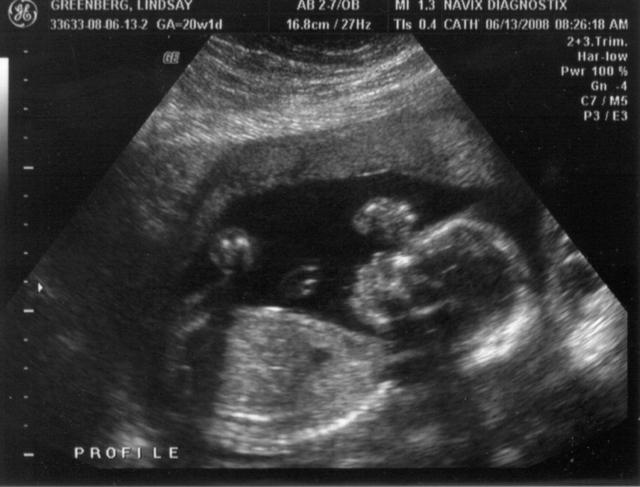

21 WEEKS FETUS WITH TRISOMY 18 (EDWARD SYNDROME), BONE ...

21 WEEKS FETUS WITH TRISOMY 18 (EDWARD SYNDROME), BONE MALFORMATIONS HIGHLIGHTED highlight specific relevance of ultrasound on bone changes in trisomy 18. The diagnosis of trisomy 18 is made by amniocentesis and genetic analysis of karyotype. ... Document Viewer